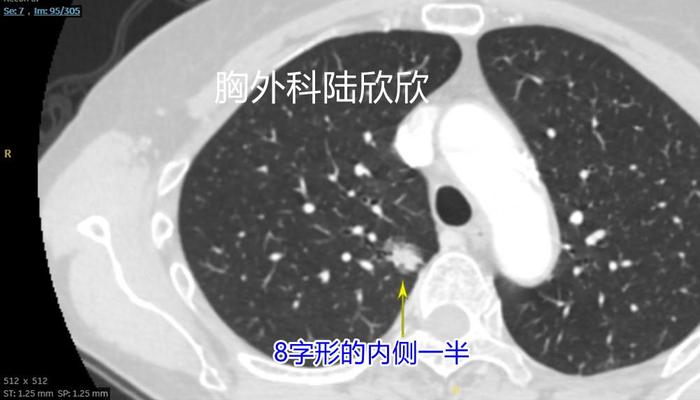

上面两张图,往下至薄层CT的95层面,可见右上肺混合磨玻璃结节的内侧半,是这个8字形磨玻璃结节的内侧半。在这个平面以实性成分为主磨玻璃成分基本上在实性成分周边。在这个层面测量结节大小为15×14毫米,这个测量是错误的。实性成分中心的平均CT值为+70,非常高。